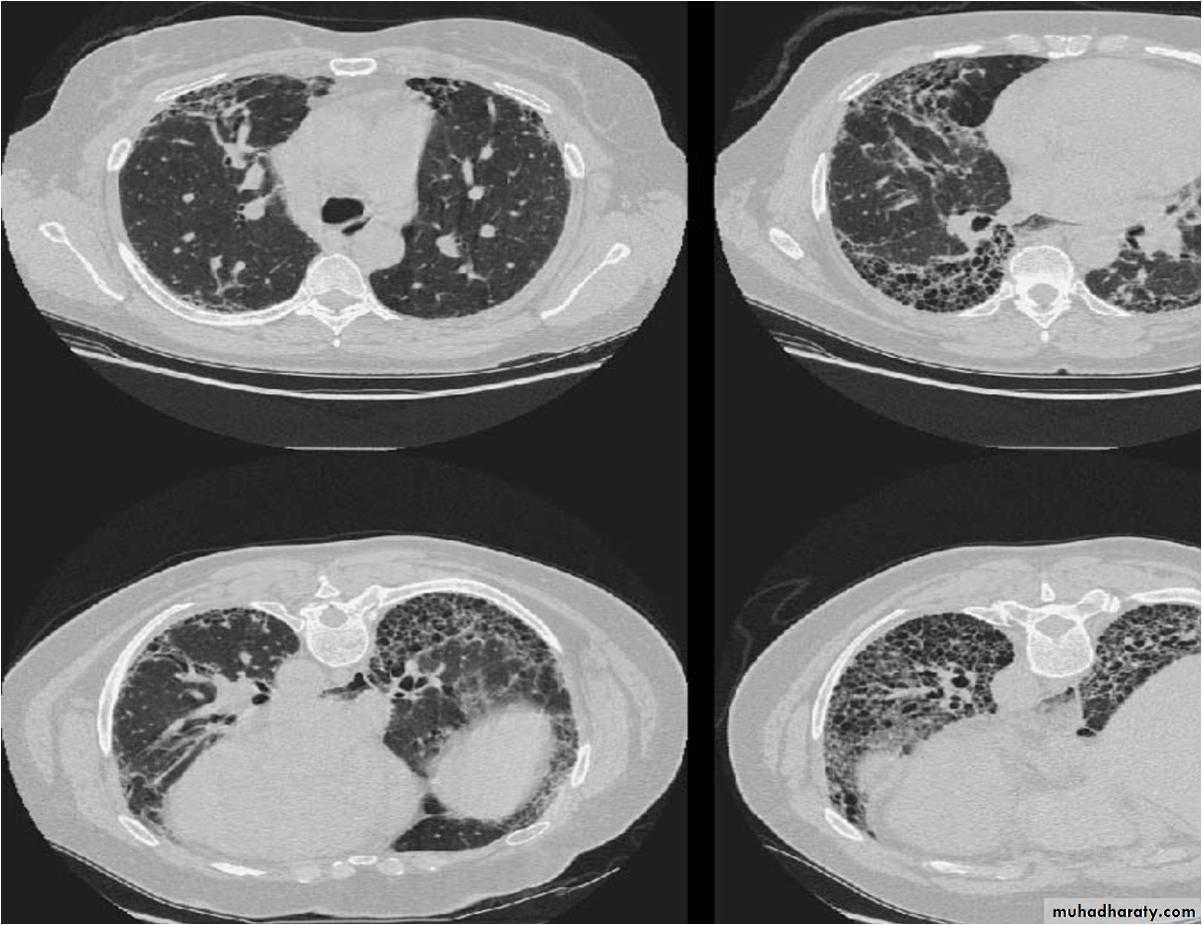

Chest X-rayLower zone shadowing

Decreased lung size

Chest X-rayAcute phase :a fine nodular shadowing

Repeated exposure :fibrotic changes more marked in the upper azones, as with sarcoidosis, than in the lower zones, as with cryptogenic fibrosing alveolitis.

Pulmonary infeltrate